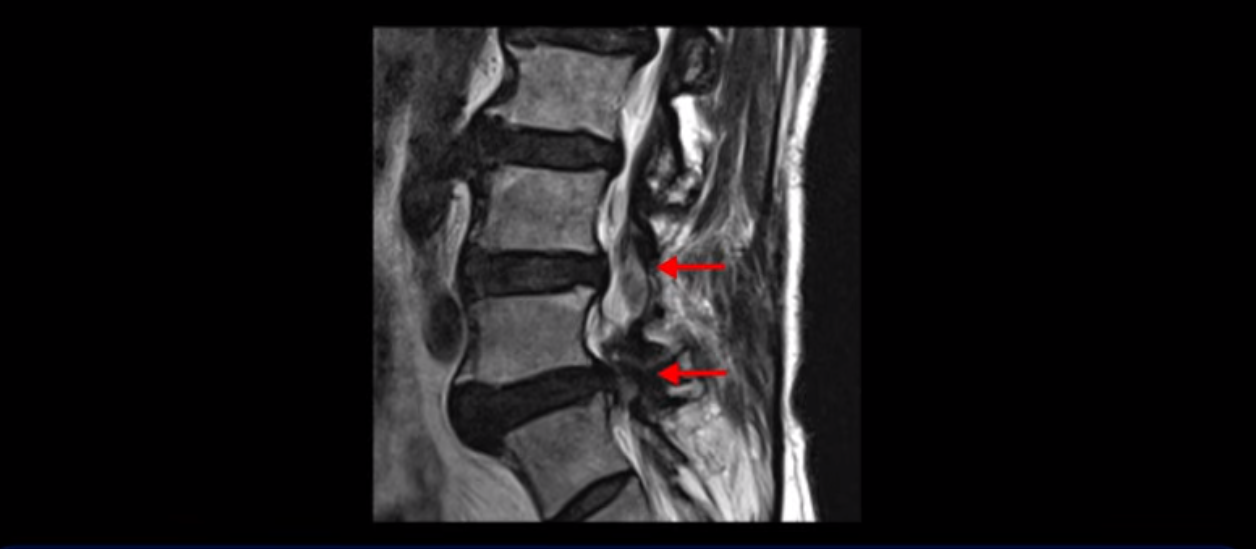

이 환자분은 협착증 수술을 두 번 받은 뒤에 또 다시 다리 방사통이 심해지고 발목 마비 증상(풋드랍)이 생겨서 이번에는 유합술을 권유받은 환자분입니다. 먼저 MRI를 보고 설명해 드린 후 이런 환자분의 방사통과 발목의 마비와 힘 빠짐이 어떻게 수술 없이도 좋아질 수 있는지 그리고 치료는 어떻게 하는지 자세히 설명드리겠습니다.

이분은 허리 다섯 마디 중 4번 5번, 5번 1번에 감압술로 눌린 신경을 풀어주는 수술을 받았습니다.

후관절을 떼어낸 흔적이 보입니다.

5번 1번도 왼쪽 후궁을 열고 수술 받았습니다.

하지만 중심성 협착은 여전히 심한 상태입니다.

이분은 오른쪽, 왼쪽 다리에 모두 방사통이 심하고 왼쪽 다리에 마비 증상, 즉 풋드랍(족하수) 증상이 있습니다. 왼쪽 신경 가지가 빠져나가는 추간공을 보면 두 마디가 좁아져 있습니다.

이런 신경 구멍이 좁아져 있는 걸 협착이라고 합니다.

이미 앞선 두 번의 수술로 뼈와 인대 등을 일부 제거해서 안정성이 떨어진 상태에서 추가로 수술하려니까 척추가 너무 불안정해져 무너질 게 걱정되니까 이번에는 나사 박는 유합술을 권유 받은 겁니다. 이런 환자분들의 방사통과 마비 증상이 어떻게 수술 없이 좋아질 수 있을까요? 치료는 어떻게 하는 걸까요?